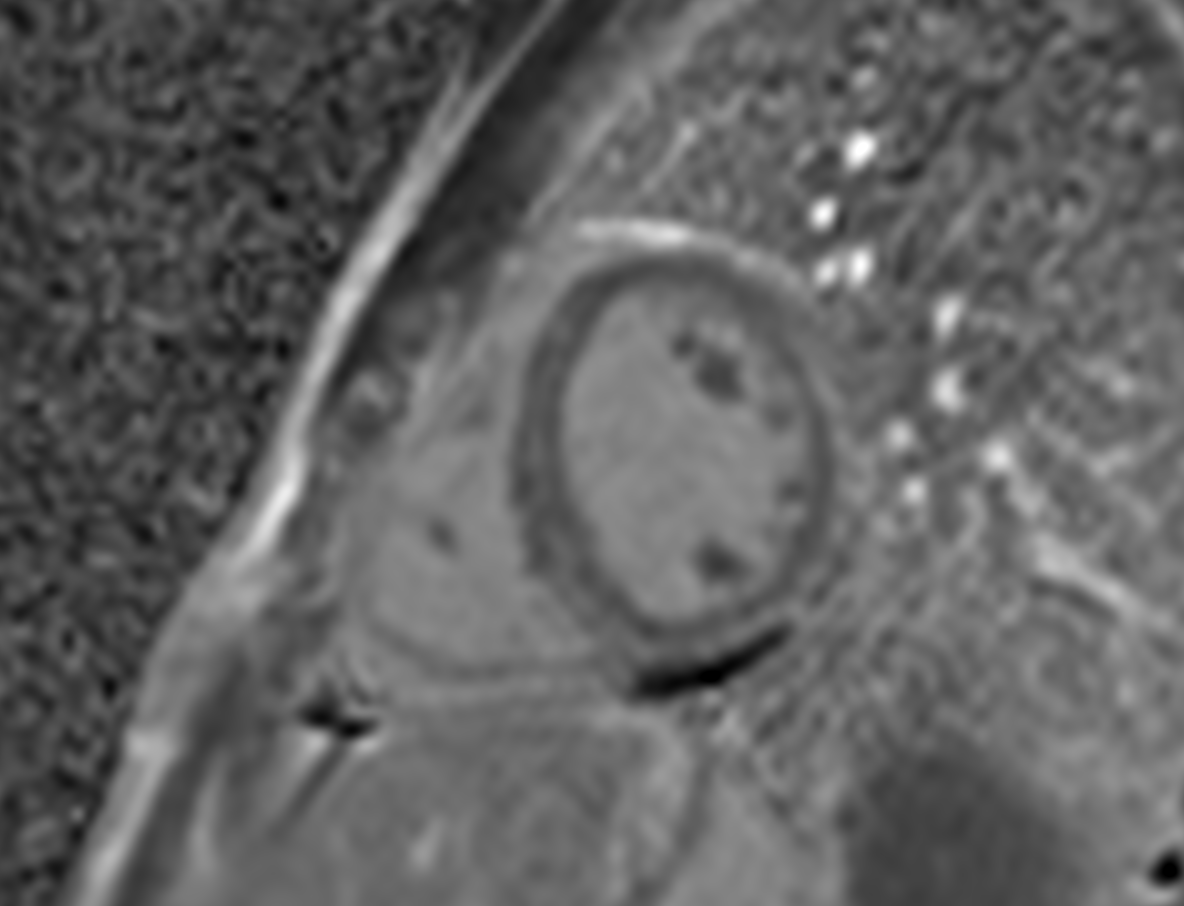

Short axis T2 maps